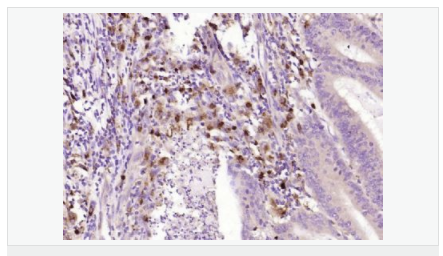

| 產品應用 | WB=1:500-2000 ELISA=1:5000-10000 IHC-P=1:100-500 IHC-F=1:100-500 ICC=1:100-500 IF=1:100-500 (石蠟切片需做抗原修復) not yet tested in other applications. optimal dilutions/concentrations should be determined by the end user. |

| 細胞定位 | 細胞漿 |